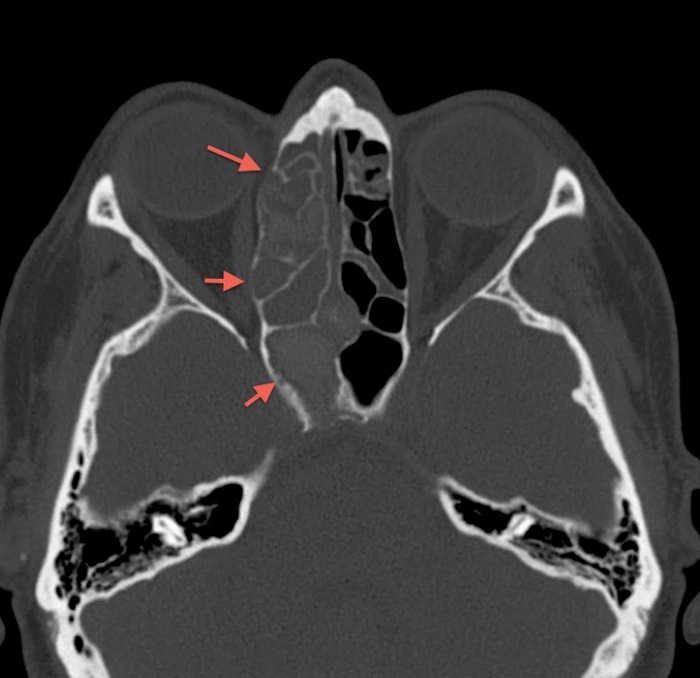

КТ-снимки хронического этмоидита: подробная визуализация